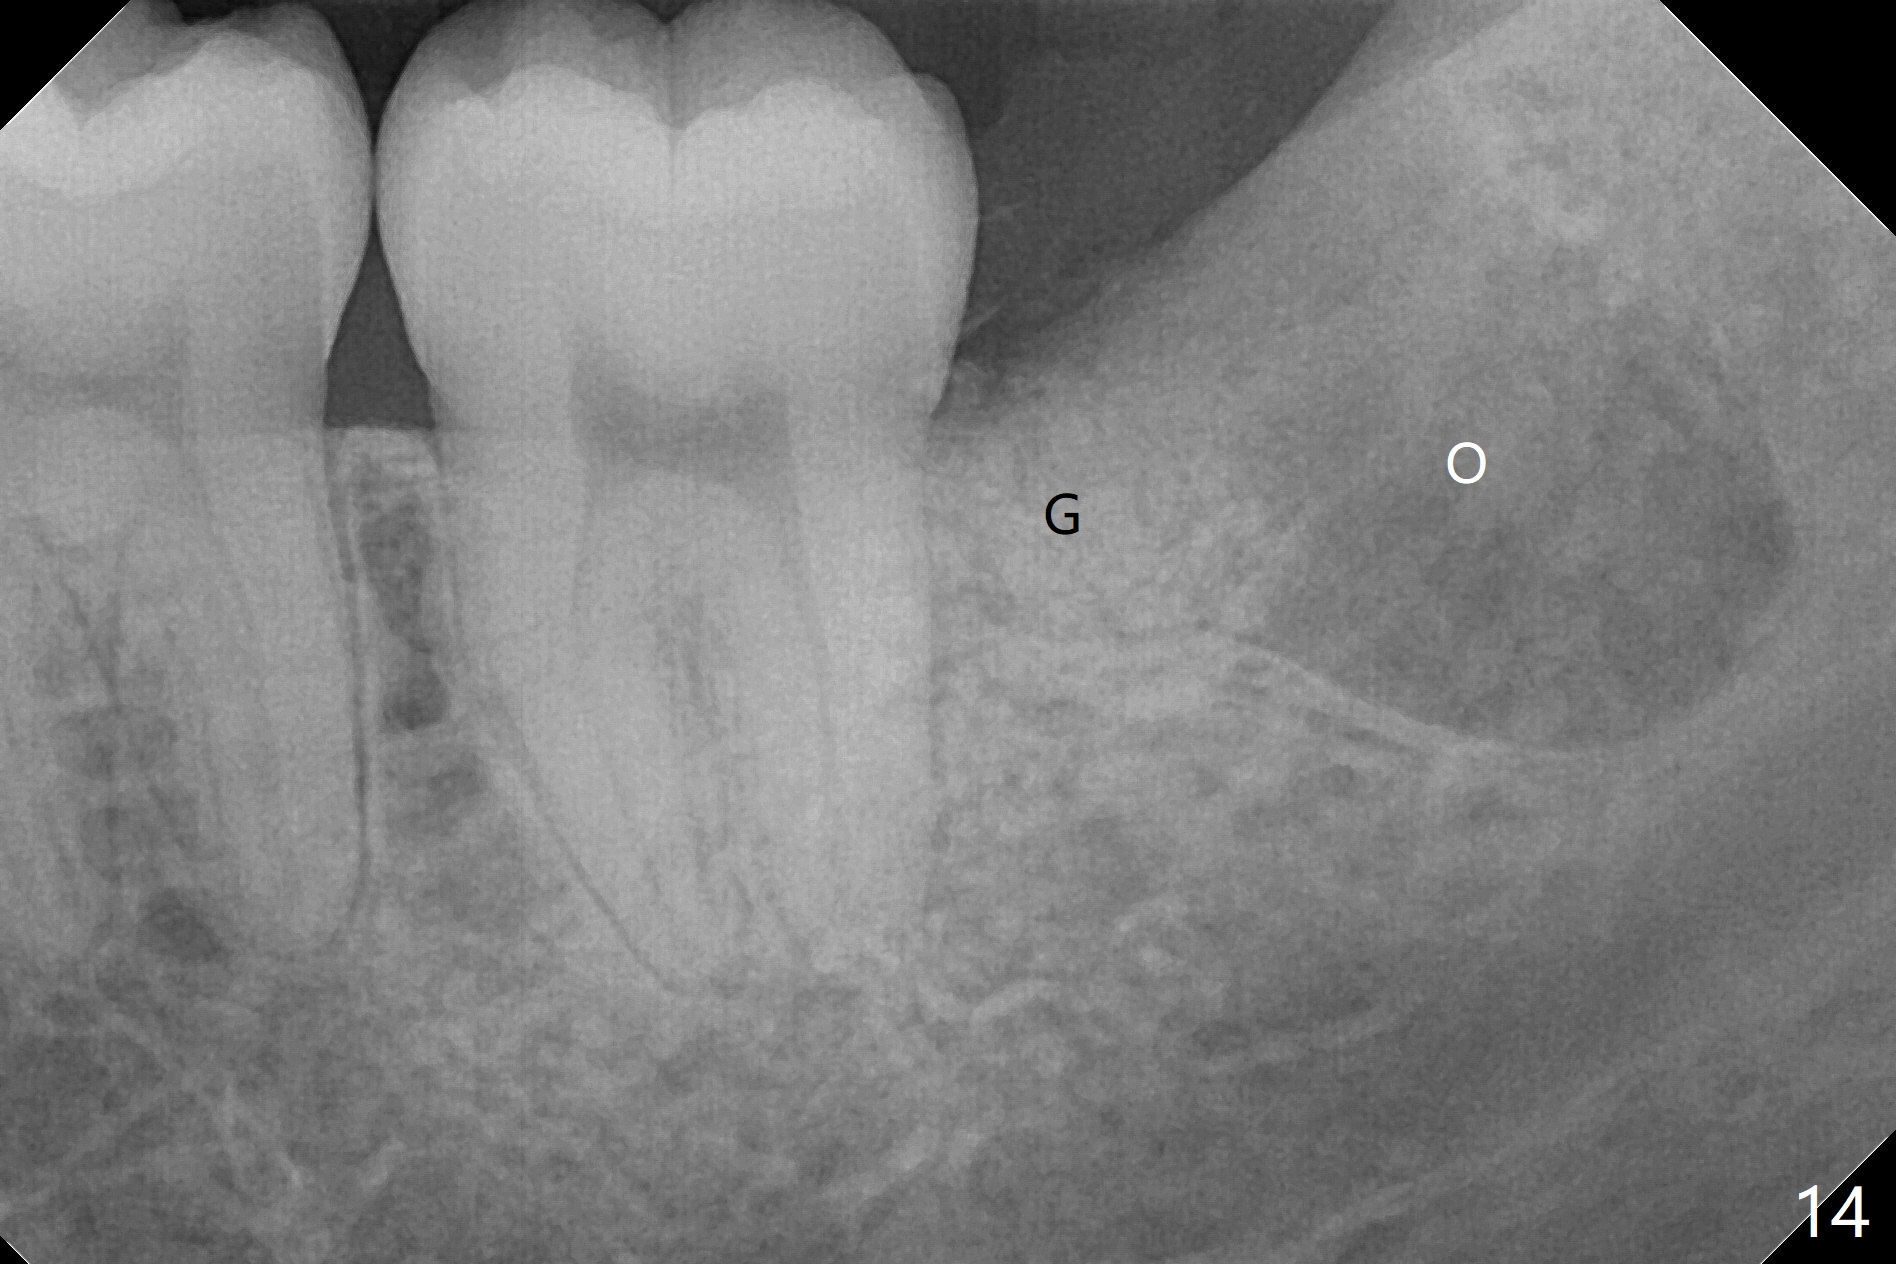

In fact the tooth #32 is extracted first; the defect involves the distobuccal aspect of the tooth #31 (Fig.4 *). An intraop PA is taken after extraction to confirm whether a broken surgical fissure bur tip retains or not; the distal lamina dura of #31 is low (Fig.5 *). It is expected to increase after cocktail bone graft (Fig.5' arrow). As planned, the bone cement (Fig.6 C) and allograft (G) are placed in the distal and mesial portions of the socket; between them is Osteogen Plug (O). Another piece of Osteogen Plug (as collagen membrane for bone graft) is placed on the top of the socket before suturing with 4-0 Plain Gut (Fig.7,7' O). Also note the bone graft being placed distobuccal (CT study) to #31 (Fig.7' red dashed line) to reduce possibility of future periodontitis. The patient returns 15 days postop with chief complaint of mild pain since extraction, although the wound looks normal. The transverse cortex connecting to the lamina dura (Fig.5 *) is obliterated when allograft is placed (Fig.7 G). The part of the graft remains in place 1 month postop (Fig.9) in spite of wound dehiscence (Fig.8). The bone graft loss is indicated by the fact of the reappearance of the transverse cortex (Fig.9). In the same appointment, the tooth #17 (Fig.10) is being extracted (Fig.11), leaving a defect mesiobuccal (Fig.12 *) to distal (curette). Part of Osteogen plug (Fig.13 O) is stretched to cover the mesially placed allograft (Fig.14 G). One quarter of Collagen plug is placed over the Osteogen plug (Fig.13 O) before 4-0 PGA suturing. There is bone regeneration 1 year postop (Fig.15,16).